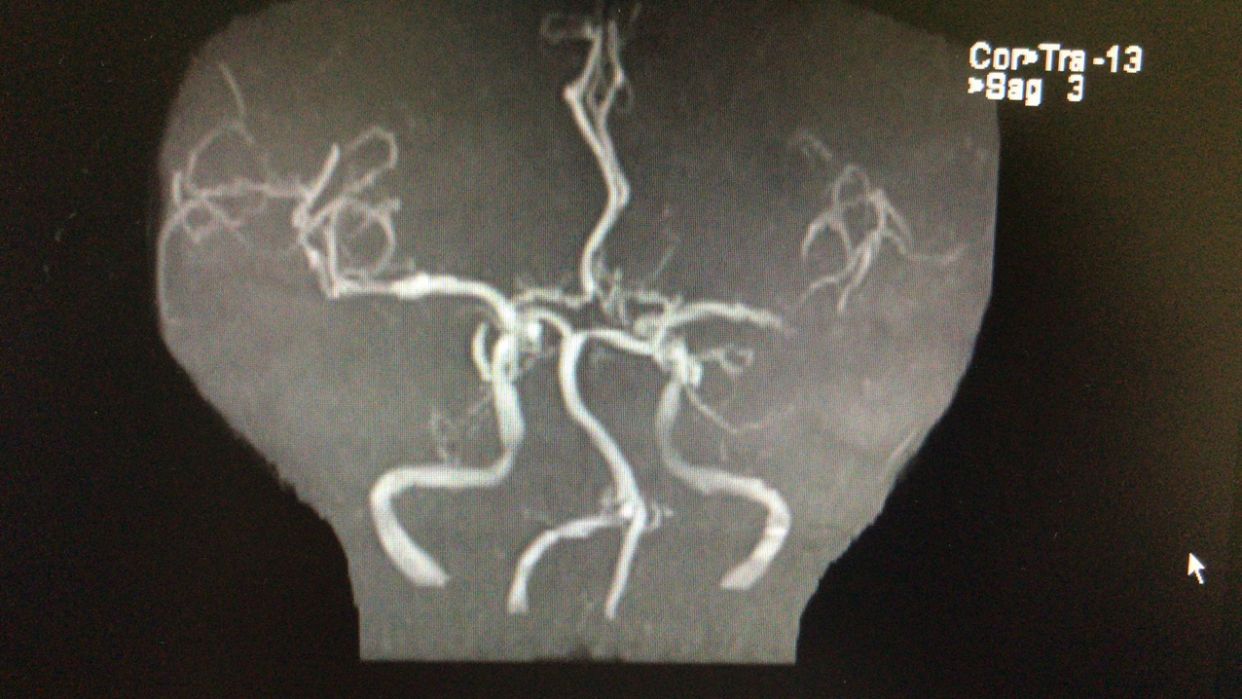

MRA示左侧颈内动脉开口重度狭窄!

左侧颈内动脉供血区显影差!